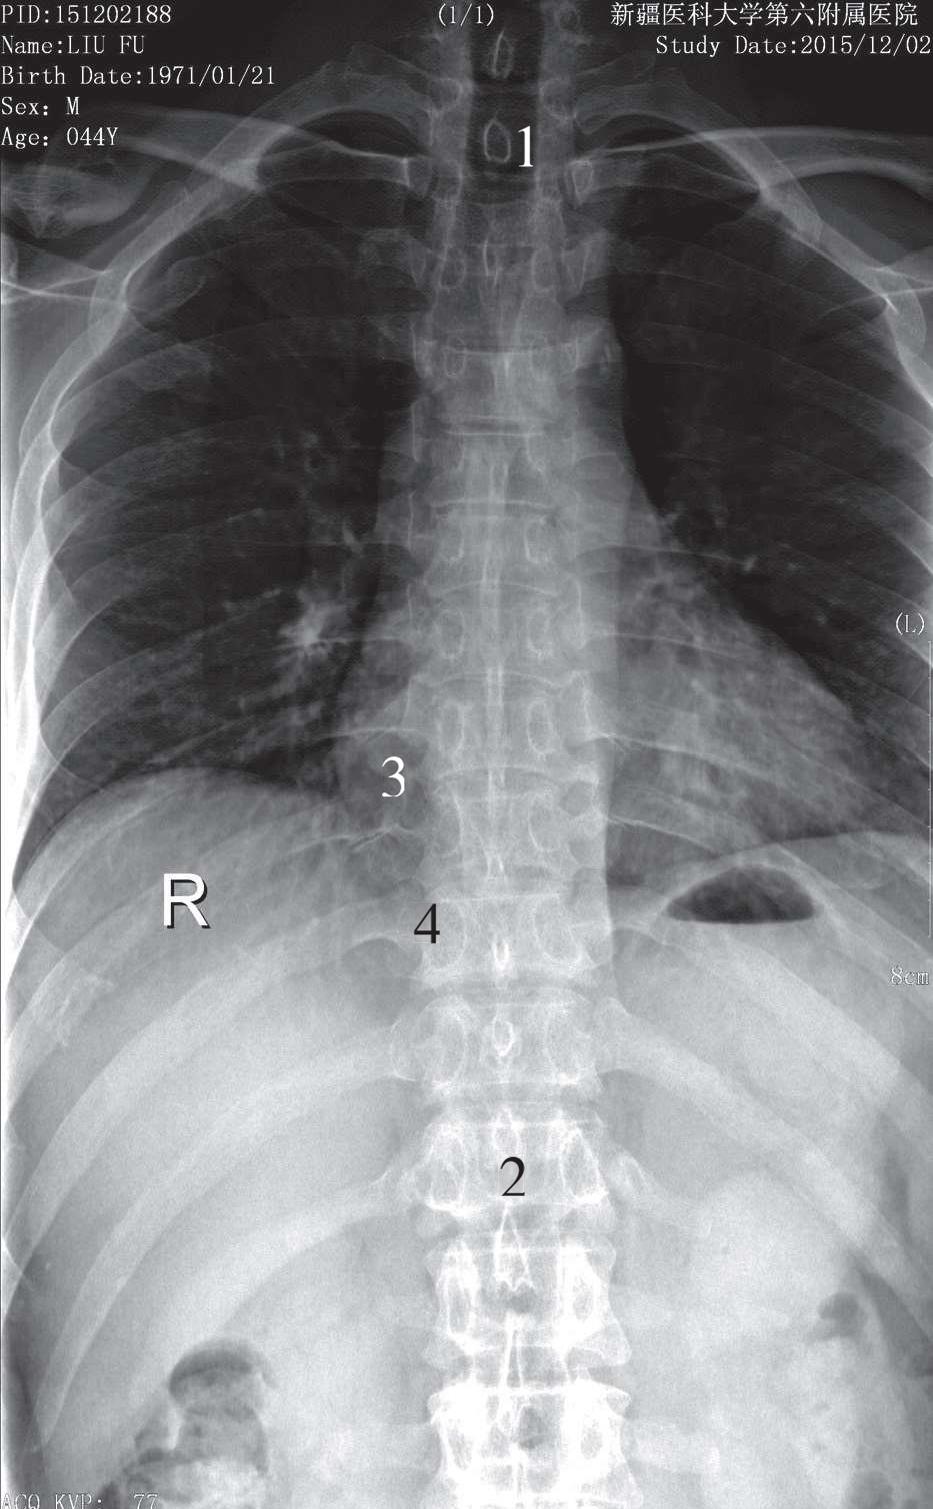

被检者仰卧于检查床上,身体正中矢状面对准检查床的中线,两臂置于身旁,下肢伸直或屈曲,影像接收器上缘平C 7 ,下缘包括L 1 ,中心线对准T 6 (相当于胸骨体中点),垂直射入,所得影像显示胸椎正位像于照片正中。胸椎椎体呈四方形,自上而下排成一排,椎间隙显示清晰,临近椎间隙大致相同,两侧横突、椎弓根对称显示,棘突位于椎体正中。胸椎两旁有12对肋骨,每根肋骨的肋骨头与胸椎椎体的肋凹形成胸肋关节(图3-11)。

1. T 1 椎体;2. T 12 椎体;3. 胸椎横突;4. 胸肋关节

图3-11 胸椎前后位片